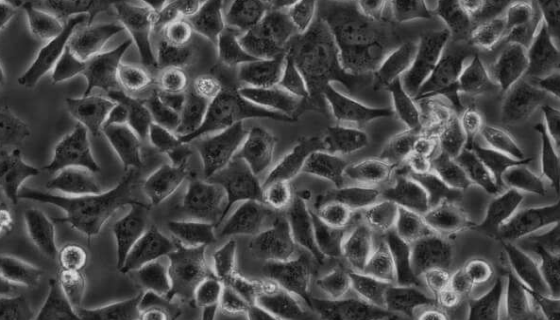

CALU-3 人肺腺癌细胞的应用与培养步骤!

CALU-3人肺腺癌细胞是从一名25岁的白人男性肺腺癌患者的...